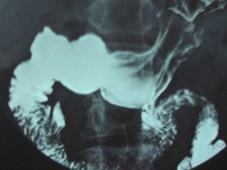

问题 女,23岁,上腹部疼痛半月,消化不良,X线检查如图,可能的诊断为 ( )

选项 A、十二指肠癌 B、十二指肠淤积症 C、十二指肠憩室 D、胃窦炎 E、十二指肠球部溃疡

答案 C